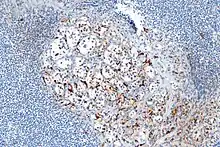

Micrograph highlighting the sustentacular cells in a paraganglioma. S100 immunostain

A sustentacular cell is a type of cell primarily associated with structural support, they can be found in various tissues.[1]